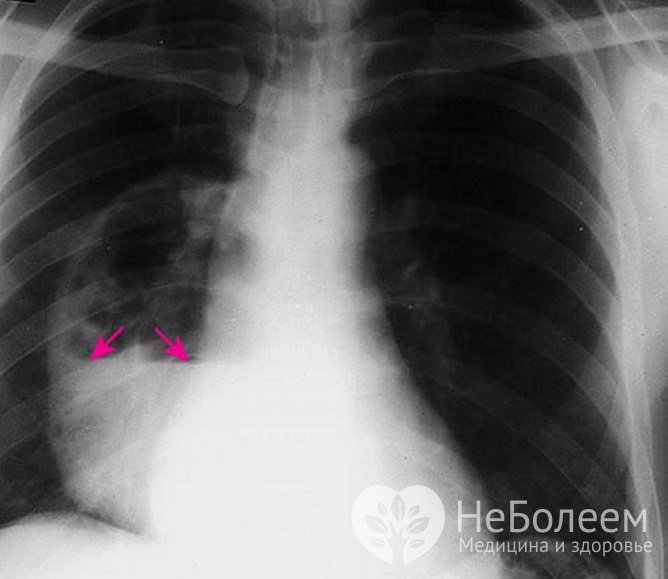

Обзорная рентгенография органов грудной клетки |

Обзорная рентгенография – один из основных методов диагностики болезни. В начальной стадии определяется гомогенное округлое затемнение, после прорыва абсцесса – округлое затемнение с уровнем жидкости (в виде корзинки). |